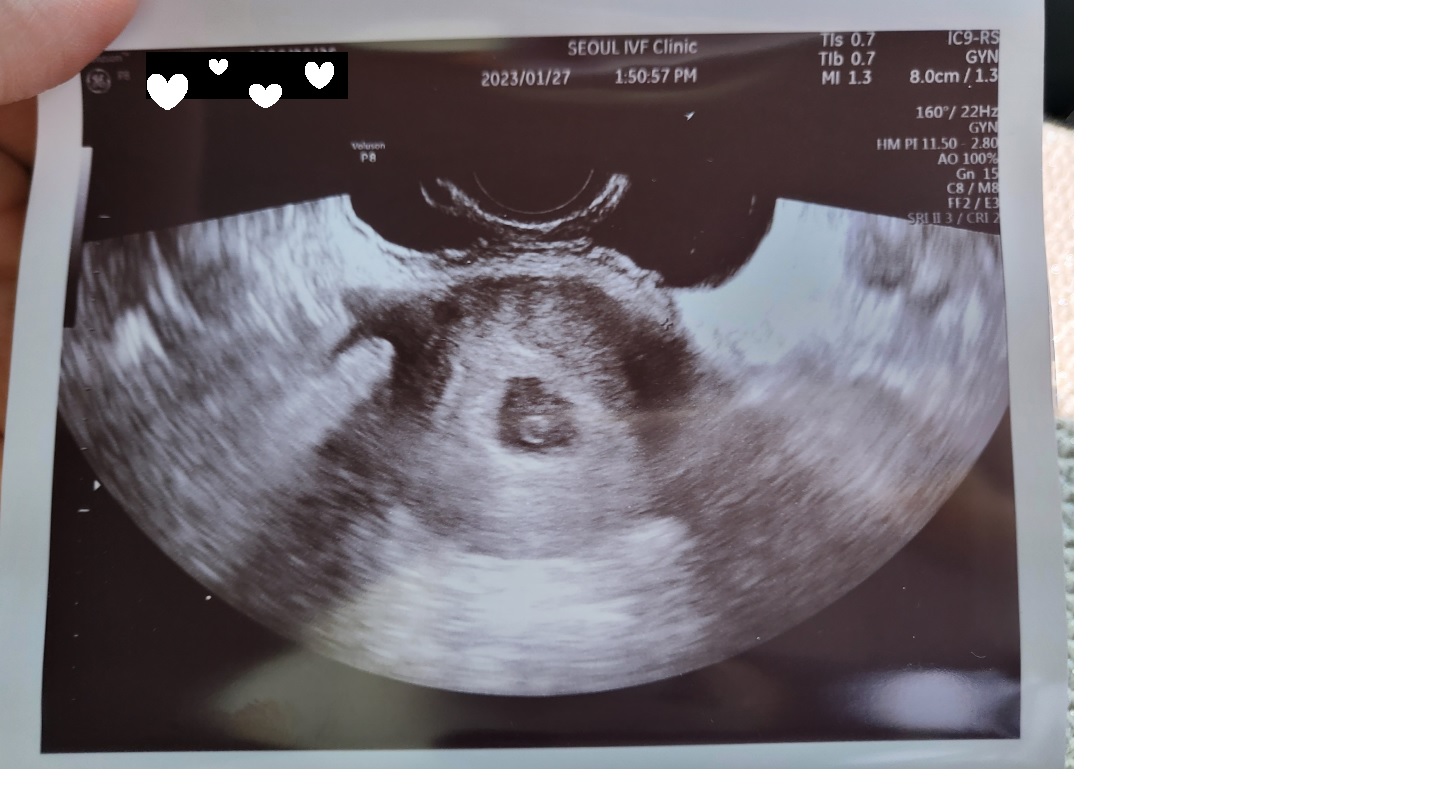

| 가슴 떨리는 임신 이야기를 공유해 주세요. | 처음 임신이 되었을때 너무 기뻤는데 그것도 잠시 6주가 지나고 피비침이 계속 되어서 결국 계류유산을 하게 되었어요. 열심히 몸 치유와 회복에 집중한 3개월 뒤에 새해를 맞이하고 23년 1월 2일에 인공수정을 진행했는데, 2주 뒤에 피검사를 통하여 286의 수치를 받고 임신에 성공하였습니다^-^* |